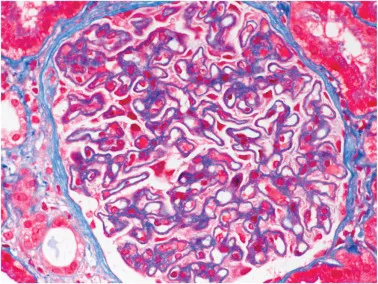

Quando pensar na possibilidade de neoplasias em pacientes com glomerulopatias? Confere esse post com dicas práticas de manejo e rastreio diante da suspeita clínica!

Luís Sette